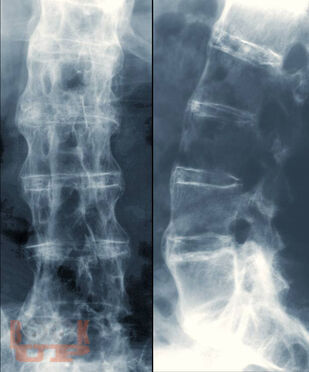

В данном учебном пособии отображены основные критерии клиники, диагностики и реабилитационного лечения суставного синдрома на амбулаторном этапе. Также представлены ведущие факторы риска развития суставного синдрома, его дифференциальная диагностика и алгоритмы ведения пациентов в условиях первичного звена здравоохранения. Отображены особенности течения инфекционного и неинфекционного поражения суставов, рассмотрены современные аспекты реабилитационного лечения данной группы пациентов. Рассмотрены вопросы профилактики и ранней диагностики поражений суставов. Учебное пособие предназначено для студентов старших курсов медицинских вузов, клинических ординаторов, участковых терапевтов и семейных врачей, врачей смежных специальностей первичного звена здравоохранения.